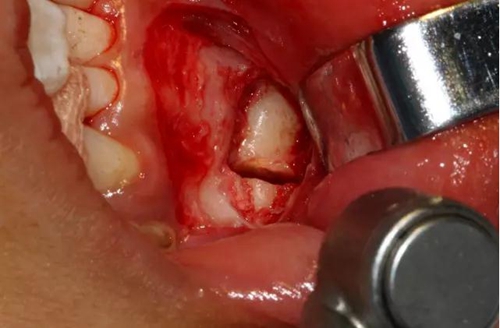

設(shè)計冠切的位置

橫斷牙冠,注意深度的把控

為了減少骨創(chuàng),“T”型分割牙冠